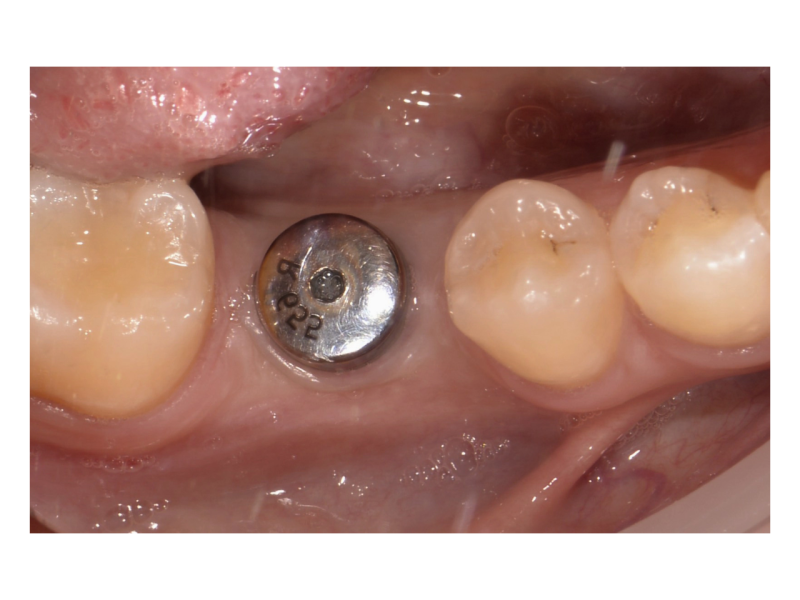

Установка коронки на зуб

Пациент обратился для завершения ортопедического этапа лечения после установки импланта в области зуба 1.4. Проведено сканирование и определён оттенок под естественный цвет зубов. Изготовлена индивидуальная коронка из диоксида циркония. Выполнена примерка, коррекция и окончательная фиксация конструкции. Проведён контроль прилегания и эстетической интеграции в зубной ряд

Доктор: Сибагатуллин Вадим Радифович